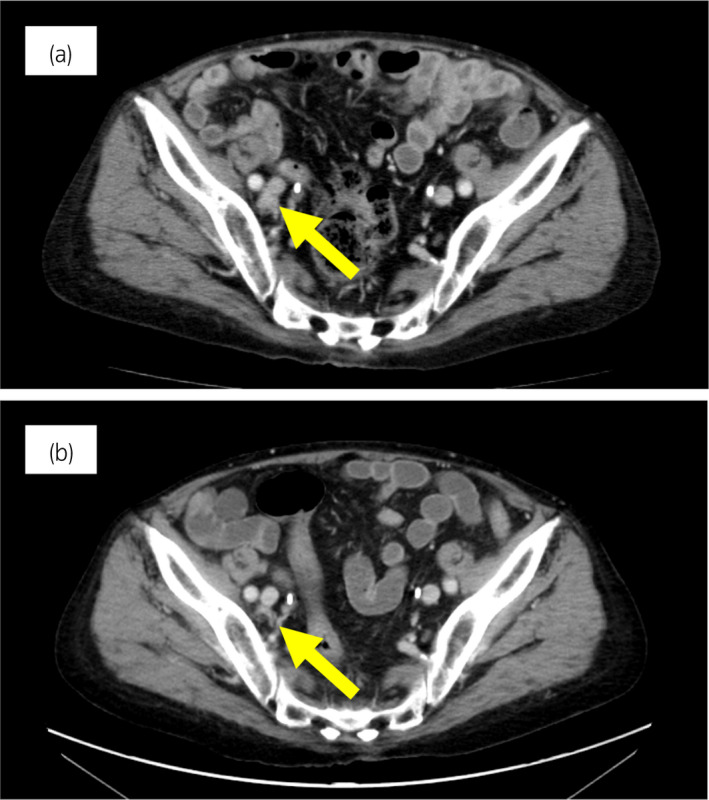

一名 78 岁男性被诊断为 cT3bN0M0,GS 为 4 + 4 =〉8,PSA 水平为 15.2 ng/ml 7 年前,并接受了前列腺切除术。 六个月后,PSA 升高并开始雄激素剥夺治疗。 两年后,开始使用比卡鲁胺治疗 CRPC。 服用比卡鲁胺五个月后,患者被转诊至佳学基因检测合作医院。 在接下来的 2 年内,依次给予恩杂鲁胺、多西他赛和卡巴他赛。 多西他赛前的 MRI 显示髂骨转移,多西他赛和卡巴他赛治疗后消失。 开始使用卡巴他赛后 6 个月,他出现双侧盆腔淋巴结肿大,并在膀胱后壁发现转移性肿瘤。 在进行经尿道切除术 (TUR) 期间,从膀胱中的转移性肿瘤获得组织样本。 病理检查显示嗜铬粒蛋白 A 阳性,NSE 水平升高,因此我们诊断为 NEPC。 卡铂和依托泊苷联合治疗缩小了肿瘤。 此后,在 24 个月内进行了 17 个疗程,疾病得到控制。 由于神经病变和疲劳而停止化疗。 随后,患者出现盆腔淋巴结转移进展(图 4a)。 通过血液检测 (BRCAnalysis®︎) 进行的基因检测对 BRCA 突变呈阴性。 使用 TUR 时收集的膀胱转移组织进行肿瘤精准用药850基因检测。 结果显示,该患者的体细胞 BRCA2 突变呈阳性。 在奥拉帕尼给药后的 3 个月内,淋巴结从 21.0mm 缩小到 7.5mm(图 4b)。 PSA 从 1.42 下降到 0.07 ng/ml,NSE 从 22.3 下降到 11.8 ng/ml。